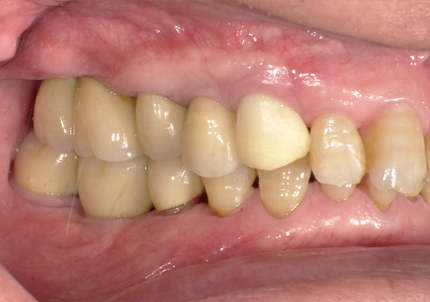

1.初診時口腔内(2007年6月30日)

↑ 2007年6月30日(初診)